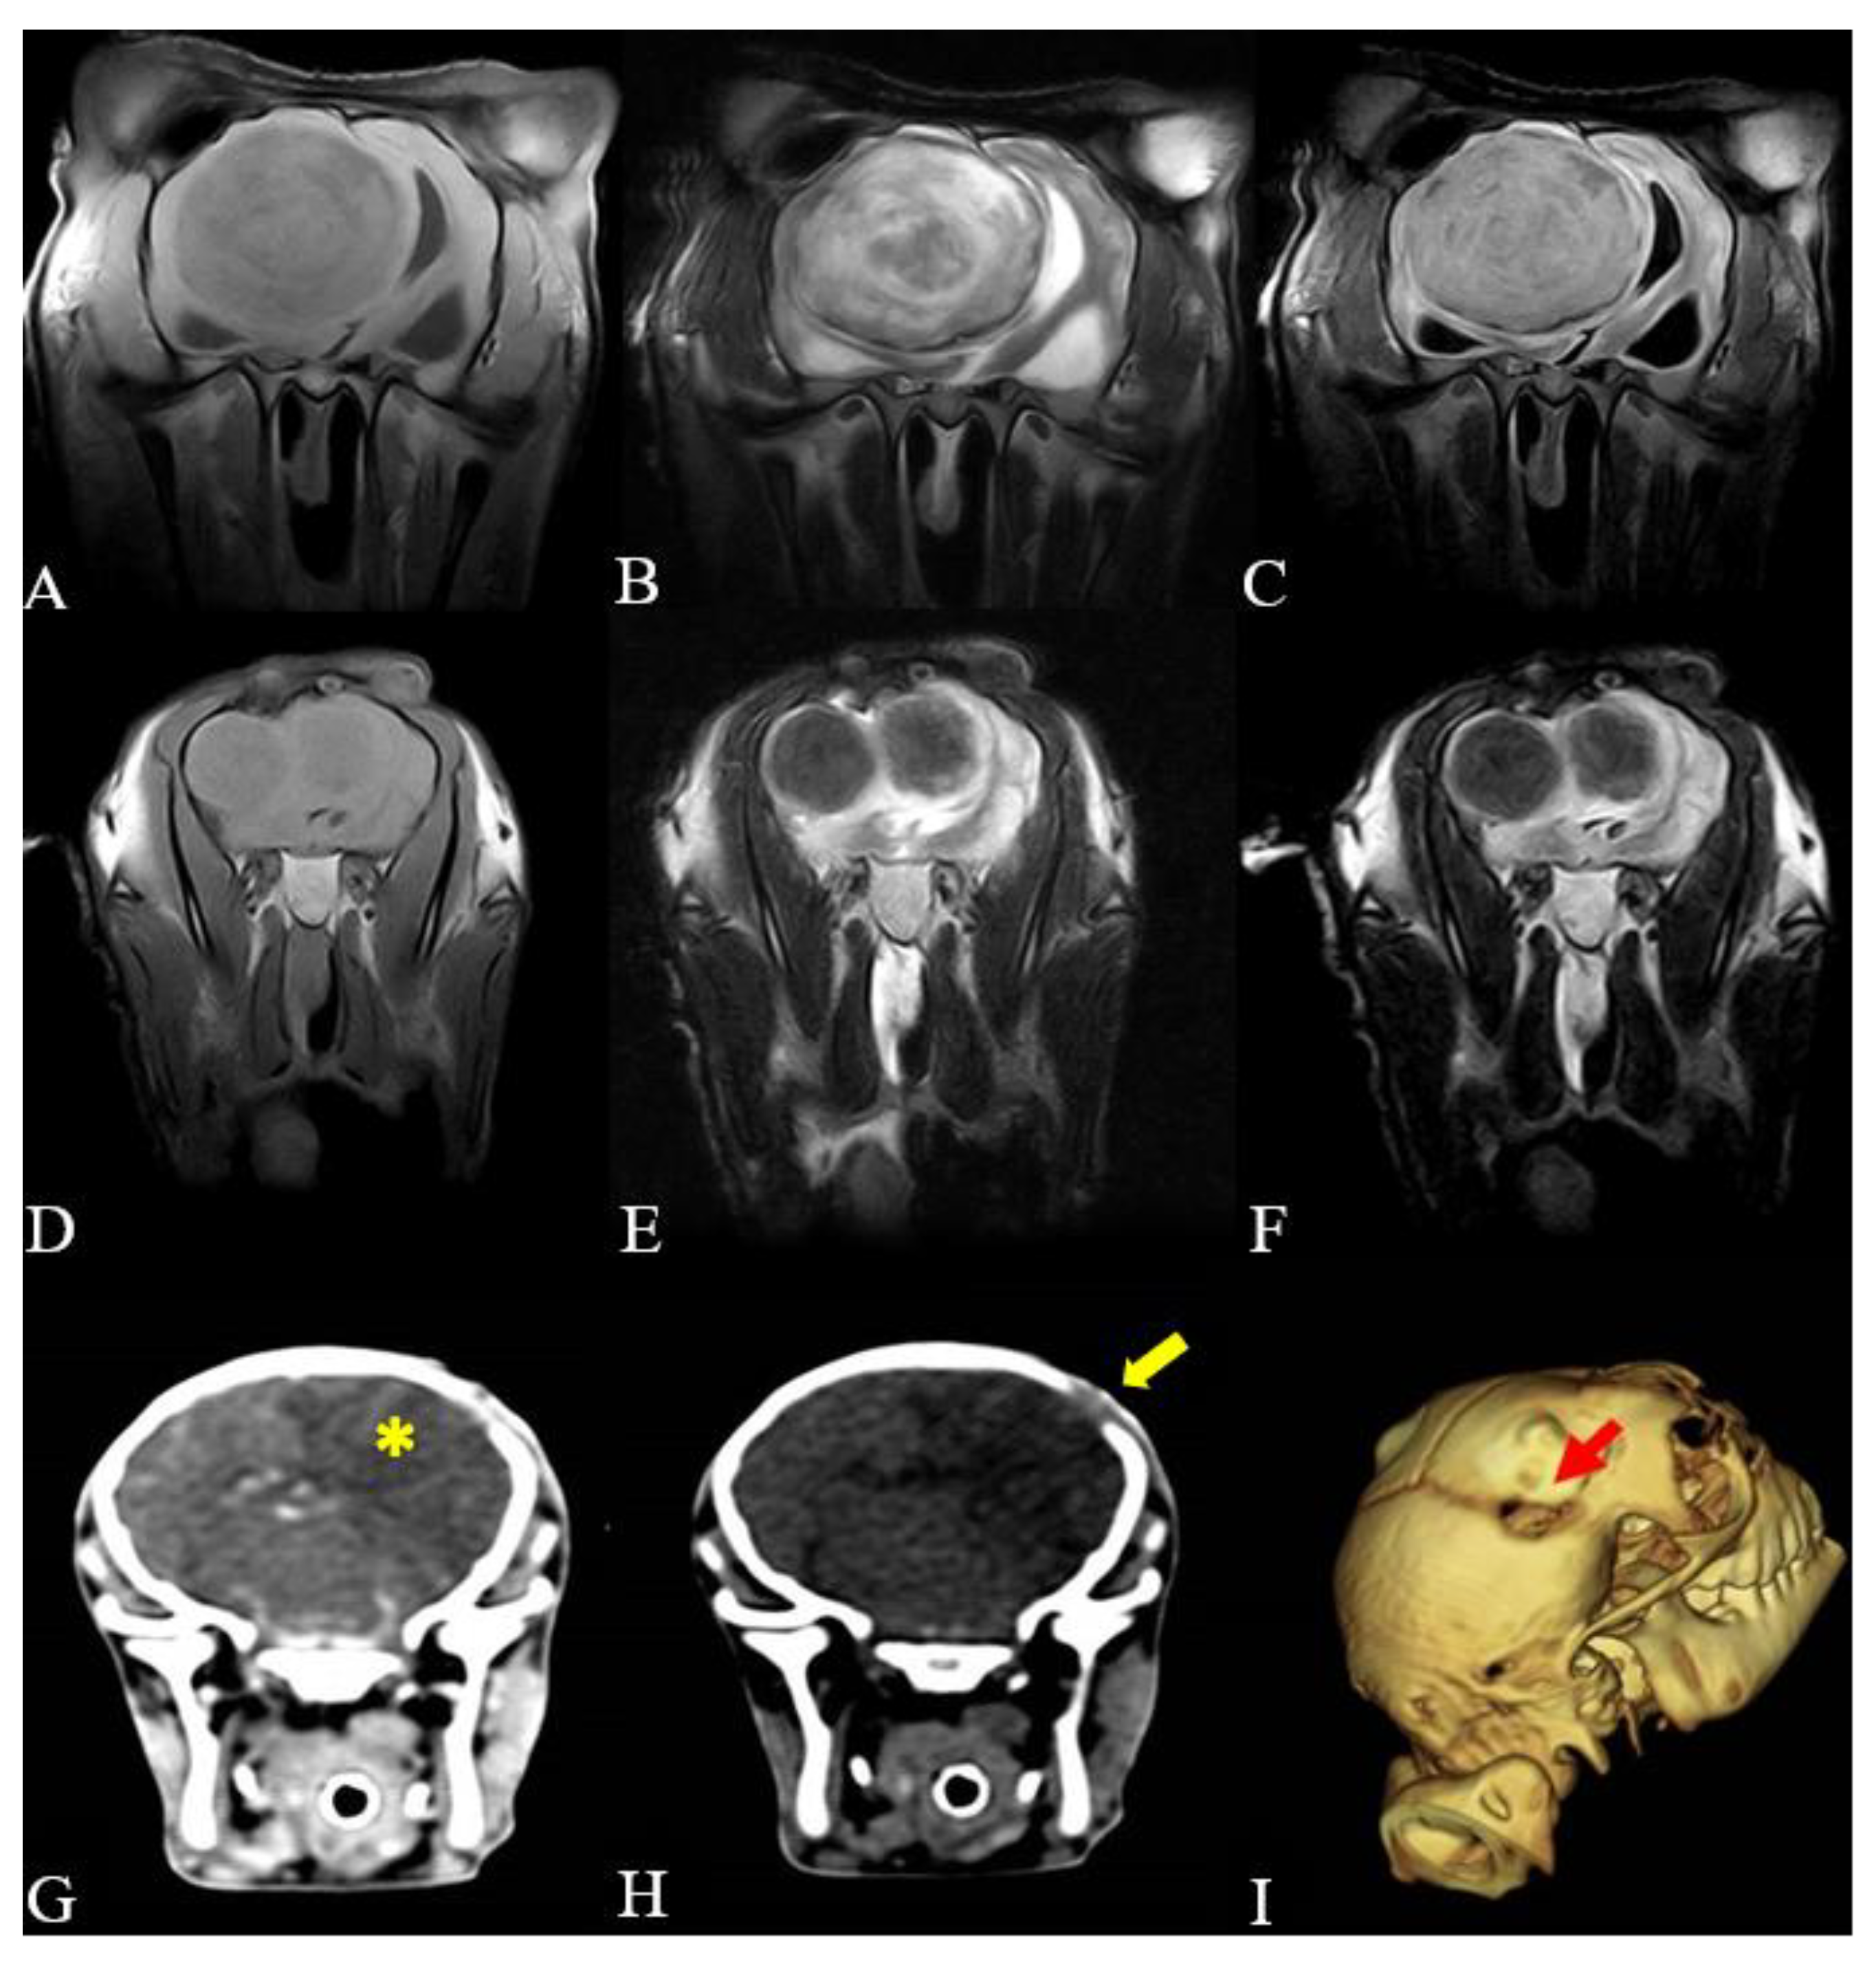

3.4. Image Findings